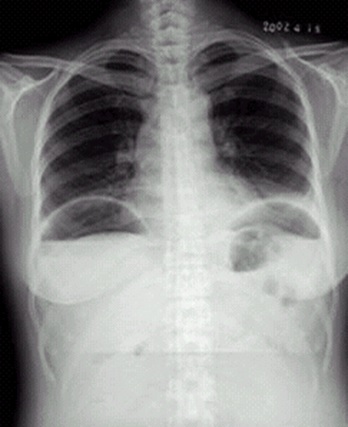

干骺端结核的X线表现【图】

膝关节结核的X线表现【图】

骨骺及干骺端结核的X线表现【图】

Colles骨折的X线表现【图】

颈椎侧位X线解剖【图】

食管裂孔疝X线表现【图】

消化道穿孔X线诊断(图)